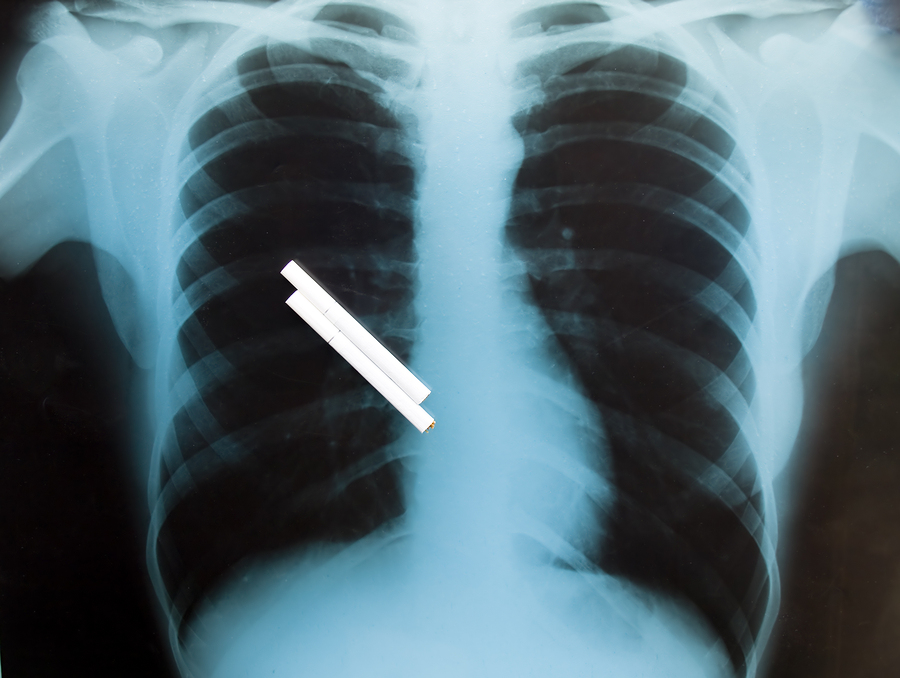

Add this one to the long list of reasons to quit smoking! Recent studies with a large number of participants have shown that people who have quit smoking demonstrated greater improvements in pain sumptoms than those who continued to smoke. Those people who did not quit smoking did not show any improvement in their pain. We have seen many patients who believe that their smoking helped them to cope with their pain, however, this data shows that in fact the opposite is true. The study also shows that people who quit smoking have improvement in pain after surgery and procedures. Quitting smoking is hard! However, there are many resources out there. The Pain & Healing institute highly recommends quitnet.com. While examinations and procedures like an MRI may come in handy, it is important to consider other external factors that are a part of your lifestyle. There are many links to resources and under the expert support tab, you can can get daily help with your goal for quitting, don’t do it alone!